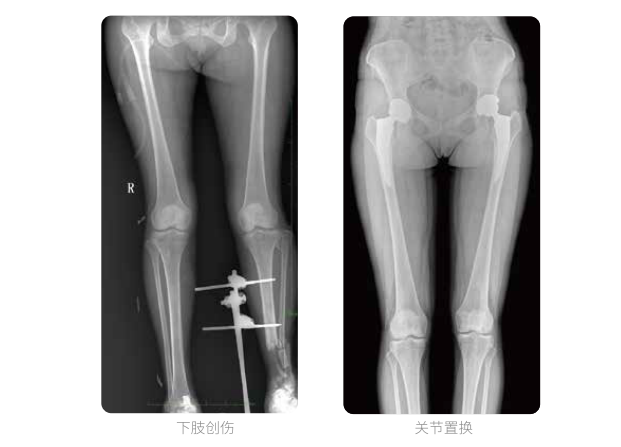

髓內(nèi)釘手術(shù)是骨科、手足外科中常見的微創(chuàng)型手術(shù)方式,患者隨訪時需拍攝置入在股骨、肱骨處的較長髓內(nèi)釘。PLX8600視野拍攝,能夠出色解決醫(yī)生需多次攝影再拼接的痛點。一次成像雙下肢,即拍即得,高效率,無需拼接。工作站軟件自帶的測量功能方便醫(yī)生讀取雙下肢長度數(shù)據(jù),助力準(zhǔn)確診斷。

動態(tài)DR所具備的全脊柱、全下肢全景成像技術(shù)檢查,能夠更加清晰的顯示患者病情變化情況,對骨科疾病患者的全脊柱、全下肢病變情況圖像展示更加具有完整性,對患者在自然狀態(tài)下的應(yīng)力情況展示較為全面,有助于骨科疾病患者臨床診斷效果的提升,對患者臨床治療方案的科學(xué)制定有著積極的作用。